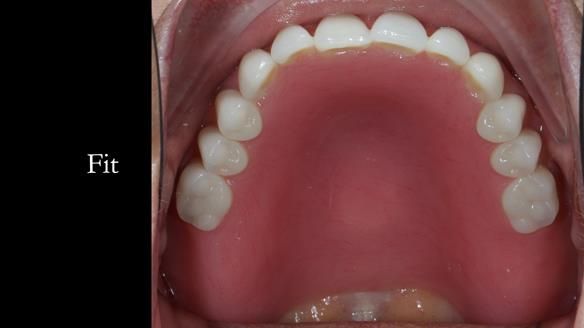

In this edition, I present the complete denture treatment for Kate, a 69-year-old American woman living in Garstang, UK. Kate had been edentulous for many years and required a set of complete dentures that closely mimicked her natural teeth. The new upper and lower dentures provided excellent retention and stability, with significant suction in the upper denture. Below, I detail the step-by-step process of her treatment, as well as my workflow for implant-supported overdentures for patients who may require them.

The treatment was a resounding success, meeting all of Kate’s expectations. While I was confident I could achieve a natural appearance, the challenges of gagging, denture stability, and eating were less predictable and uncertain. I discussed these concerns thoroughly at the outset, and Kate decided to proceed despite the high cost. She expressed that there was no pressure to move forward with the treatment, and she’s been delighted with the life-changing results.